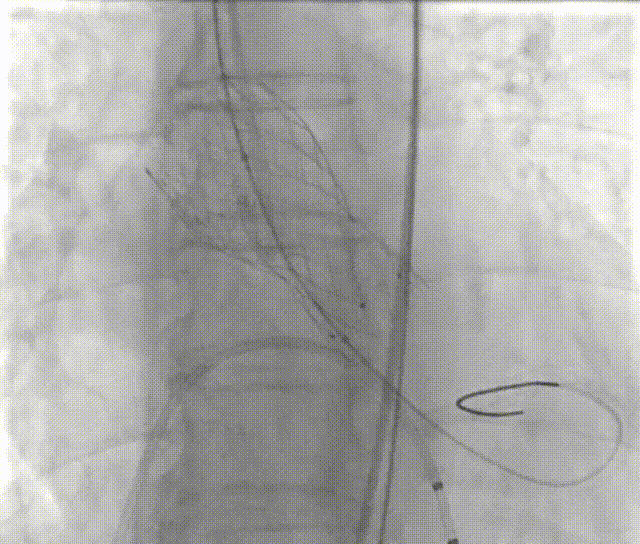

手术过程